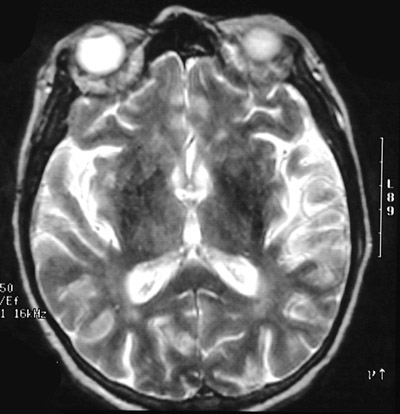

![]() | This T2 weighted MRI scan in axial view reveals a carcinomatous meningitis characterized by thick areas of brightness overlying the cortex and in the sulci. Breast carcinomas can, on occasion, metastasize in this fashion, but other cancers can rarely do so as well. |